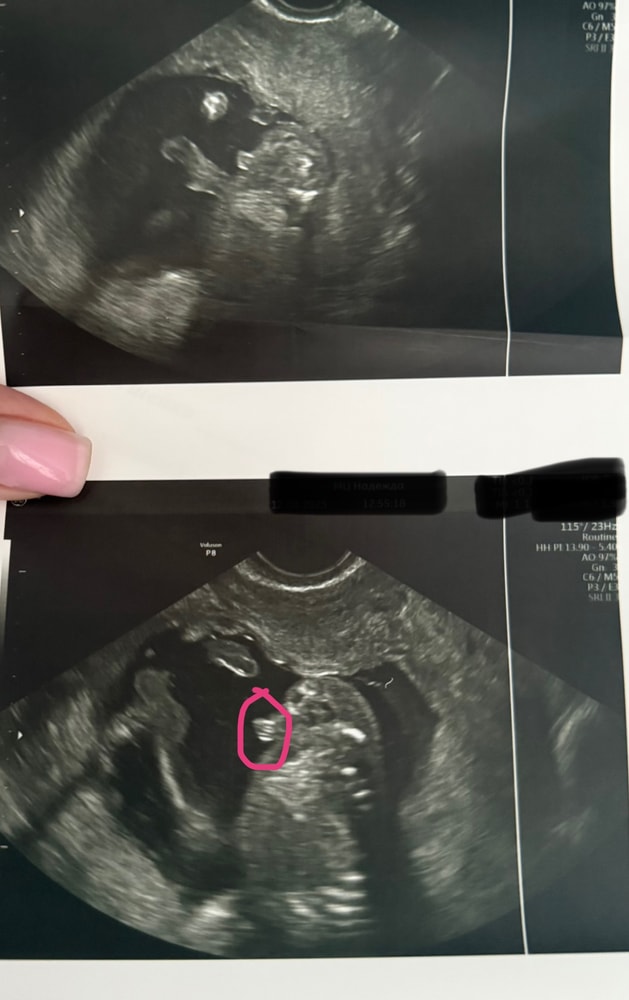

УЗИ, КТГ, доплерПоказала значит я фотки с узи своим подружкам мол ждем мальчика,а они мне начали говорить,что похоже на девочку больше.Либо с беременностью я стала более внушаемой,но теперь сомневаться начала и мой беременный мозг уже сносит🥲Врач четко показала на узи между ног,что есть 🔔🔔 и я четко видела.Еще раз приложу фотки узи,обвела что врач имела ввиду.Это ракурс как раз между ножек.Сказала у девочки не может так за контуры тела выходить.Короче,девочки кто разбирается в узи успокойте меня и мое любопытство.Хотели уже родных собирать пока тепло сообщать о внуке,а теперь во мне сомнение затесалось.Ну мальчик же,нет?Умоляю,не пишите про сдачу крови только.Если бы я знала,что так долго надо будет ждать и терпеть,то сдала бы уже на 10 неделе и не мучилась(